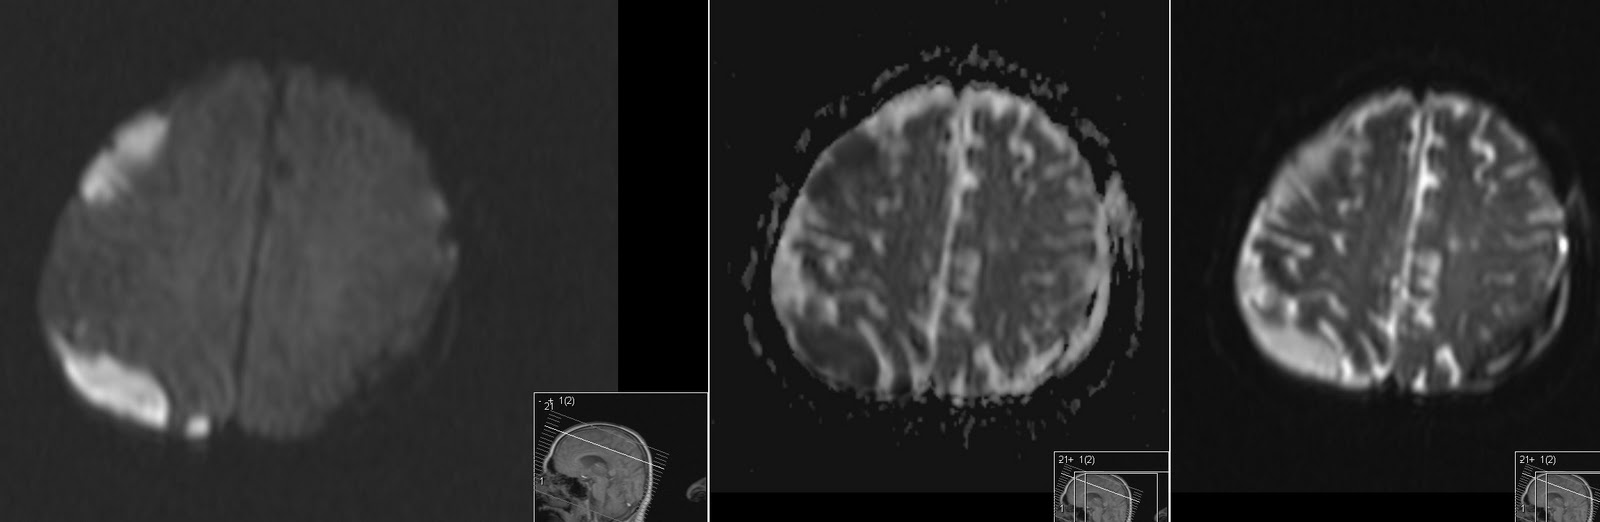

From radiologymri.blogspot.com

Radiology MRI Abscess and Subdural Empyema Abscess Vs Empyema these features are helpful in distinguishing a pulmonary abscess from an empyema (see empyema vs pulmonary abscess). In many patients with pneumonia,. empyema is defined by purulent fluid collection in the pleural space, which is most commonly caused by pneumonia. empyema is a condition that causes pus to develop in your pleural space, usually due to pneumonia.. Abscess Vs Empyema.

Radiology MRI Abscess and Subdural Empyema Abscess Vs Empyema a lung abscess involves the lung parenchyma, whereas an empyema involves the pleural space. the most reliable ct features for the differential diagnosis of lung abscess and empyema were wall characteristics,. In many patients with pneumonia,. Learn how to diagnose and. empyema is a condition that causes pus to develop in your pleural space, usually due to. Abscess Vs Empyema.